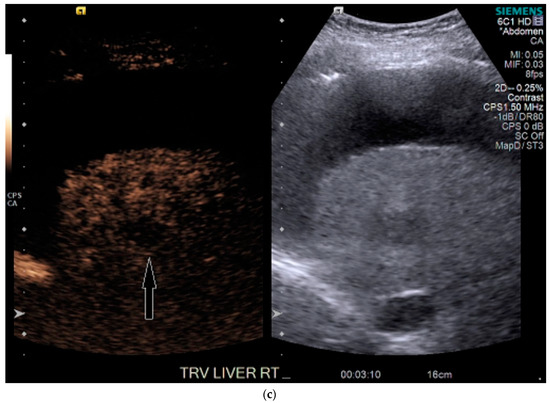

His liver function continued to decline during his stay, and within two weeks he received a deceased donor liver transplantation. HCC within the explanted liver was confirmed by histopathological examination, corresponding to the findings on CEUS. Upon review of the prior CT, for which a reduced contrast bolus (75 mL Omnipaque™ 350) was given due to his chronic renal disease, the tumor was subtle but faintly visible with the knowledge of its location based on the findings on CEUS (Figure 6).

Figure 6.

Patient 3 CT images using liver windows to highlight the subtle enhancement and washout of the lesion seen on CEUS (white arrow): (a) late arterial phase axial contrast-enhanced CT; (b) 3 min delayed phase.

In our third case, the lesion was not seen on the prior CT. This may have been due to location, and a lower dose of intravenous contrast that was used due to the patient’s impaired renal function. Interestingly, this lesion was well seen with CEUS, despite its challenging location at the dome, which can be a blind spot in US. We postulate that the ascites may have aided the CEUS exam—even though it increased the depth of the lesion, the ascites created a window to view the lesion, even with patient breathing, both of which would have negatively impacted on MRI.